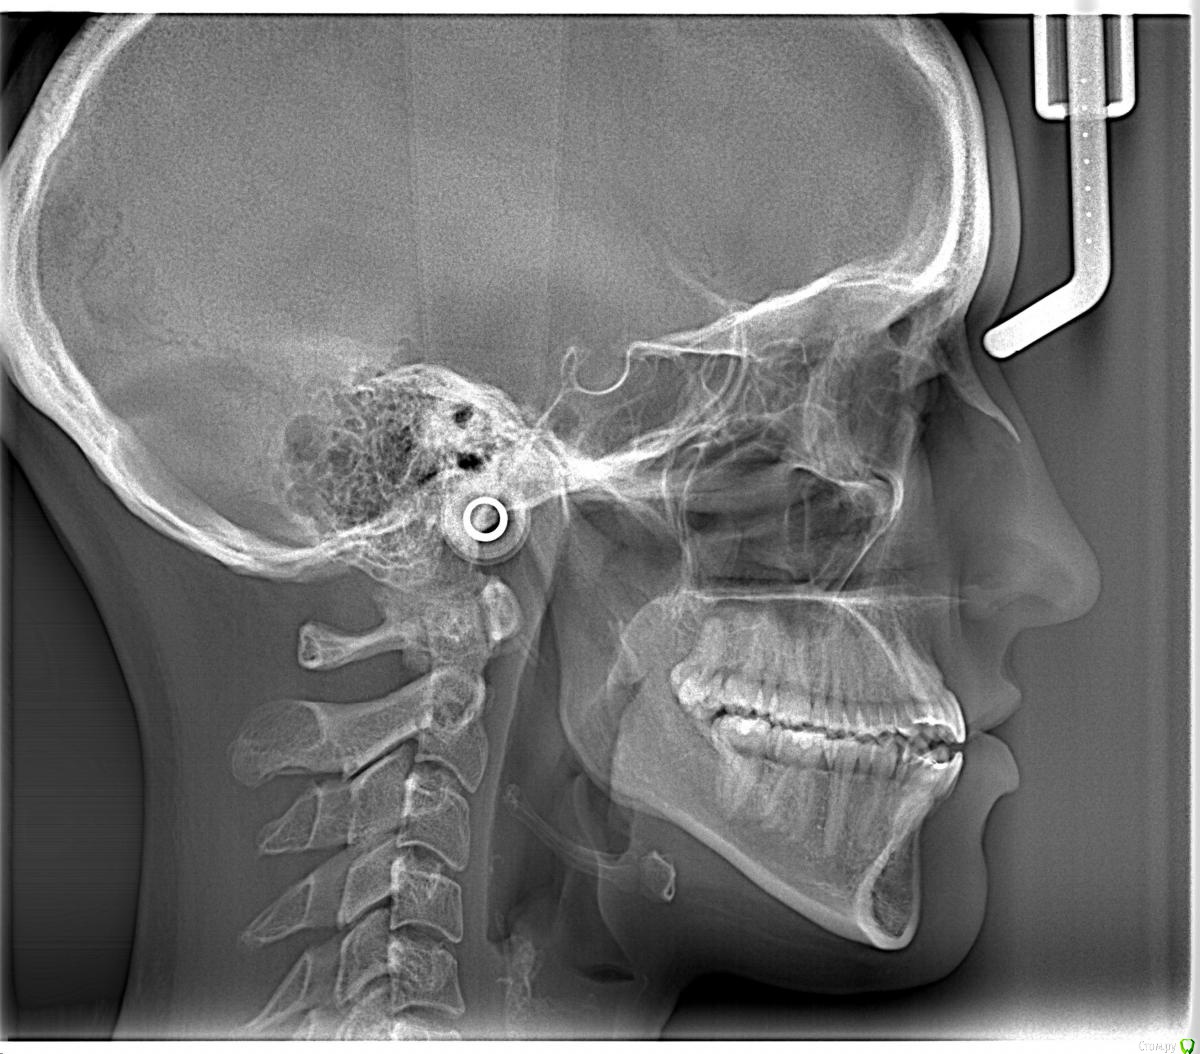

Opdihatop Опубликовано 4 марта, 2017 Поделиться Опубликовано 4 марта, 2017 И снова здравствуйте, коллеги. Вот такой вот случай к рассмотрению. Много лет назад пациентка уже проходила "камуфляжное" лечение. Со слов пациентки оно было закончено с передним открытым прикусом. Сейчас ситуация такая. Пациентка думает над ортохирургией, но меня смущает фронт н/ч. И по снимкам и по ситуации во рту корни 32, 31, 42, 43 зубов фенестрировали лингвальную кортикалку почти на всем протяжении, 33 - вестибулярную. Вопрос вот в чем: что делатьс этими зубами? Возможно ли их поставить на место? Или лучше не трогать, дольше простоят? Ссылка на комментарий

Brigita Опубликовано 4 марта, 2017 Поделиться Опубликовано 4 марта, 2017 не трогать - в смысле перед ортогнатикой только верх лечить? Ссылка на комментарий

Opdihatop Опубликовано 4 марта, 2017 Автор Поделиться Опубликовано 4 марта, 2017 не трогать, в смысле вообще не трогать, даже хирургически. Боюсь потерять весь фронт н/ч Ссылка на комментарий